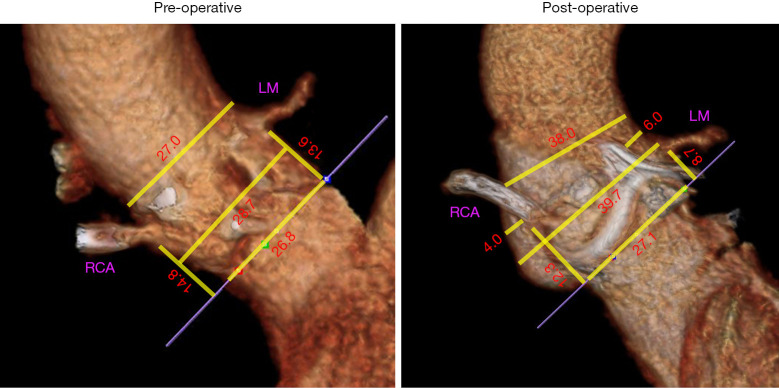

Results: Average age was 65±11 years, the majority were female (29, 64%), and 9 (20%) had undergone prior aortic valve replacement (AVR). Valve upsizing was ≥3 sizes in 41 (91%). Post-operative mean basal ring diameter was larger compared to the native annular diameter (26.3 vs. 25.3 mm, P<0.01) and substantially larger than prior prosthetic valve in redo AVR (25.6 vs. 19.3 mm, P<0.001). Diameters of the sinuses at pre-operative computed tomography (CT) increased by +7.7±2.8 [right sinuses of Valsalva (R SVS)], +6.7±3.0 [left sinuses of Valsalva (L SVS)], and +6.6±2.9 mm [non-coronary sinuses of Valsalva (N SVS)]. Mean diameter of the STJ increased to 38.3±3.7 post-operative (+8.1±3.2 mm). Left main (LM) and right coronary artery (RCA) heights decreased by -6.3±3.3 and -3.7±3.4 mm respectively due to the supra-annular position of the valve, however, the post-operative valve-to-coronary (VTC) artery distances were 6.6±2.3 and 4.9±2.0 mm, respectively.

Conclusion: The Y-incision root enlargement technique significantly enlarges the sinus and STJ diameters by 6-7 mm while preserving VTC distances despite upsizing by 3-4 valve sizes, resulting in post-operative anatomy that is favorable for future transcatheter aortic valve-in-surgical aortic valve (TAV-in-SAV).